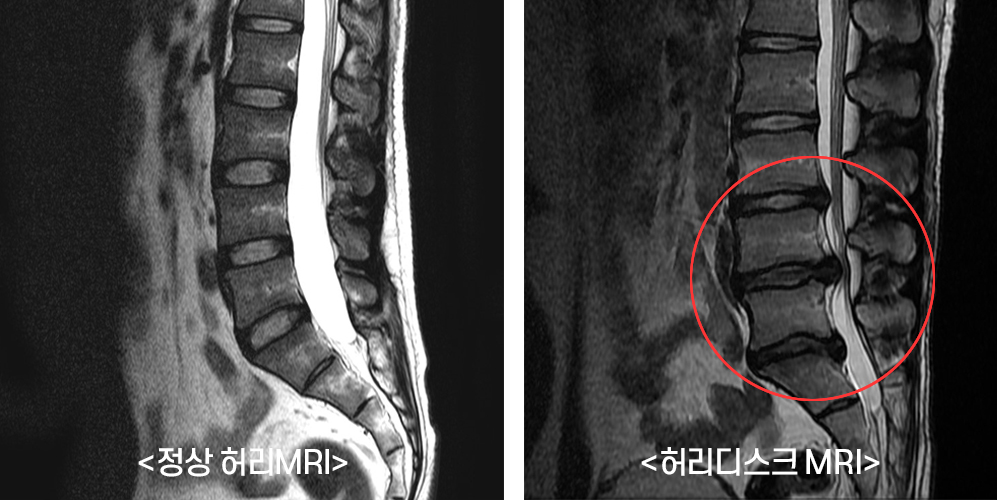

이번 포스팅에서 허리디스크에 좋은 운동 10가지에 대하여서 알아볼꺼에요. 허리는 우리 몸무게의 약 60%를 지탱하고 있습니다. 상당히 귀중한 육체 부위에요.

사무실이나 집에서 컴퓨터나 노트북을 하는 직장인들이 많다고 해서지면서 허리디스크 통증을 호소하는

분들이 불어나고 있다고 합니다.

허리디스크에 대해 아직 살펴보지 못하셨다면 허리디스크가 어느 부위를 말하는지 확인하시고 시기에 맞추어 운동하여 주십시요.

서울대 재활의학과 교수님이 쓴 책의 내용인데 1주일에 20km 이상을 달리는 사람과 운동은 하지 않는 사람들을 비교해 봤을 때, MRI 영상에서 달리기를 꾸준히 하는 사람들이 허리디스크가 두꺼웠고 그 속의 수분 함유하고 있는 분량이 높았다는 내용이 있었습니다.